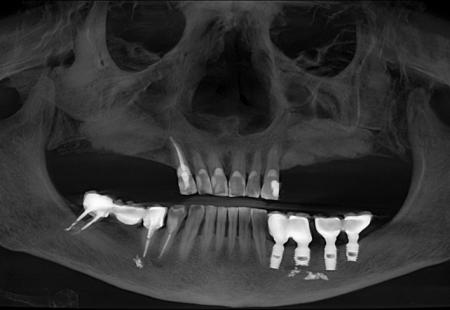

Совместные работы врача стоматолога-хирурга Семеновой Ксении Сергеевны и врача стоматолога-ортопеда Лежениной Елена Святославовна, зубной техник Дрындин Вячеслав

Реабилитация в течении одного года. Два комплекта временных коронок, дентальная имплантация на верхней челюсти по хирургическому шаблону, одномоментная нагрузка в течении 5 дней. Постоянное протезирование керамическими коронками из диоксида циркония

Протезирование керамическими коронками из диоксида циркония на имплантах

Тотальная фунцкионально-эстетическая реабилитация пациента по системе все на all-on-6

Планирование и протезирование проведено полностью в цифровом протоколе.